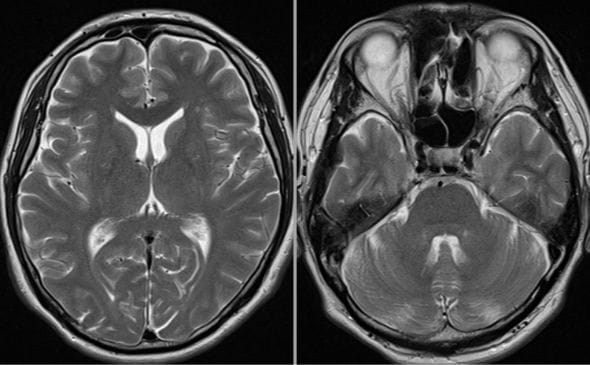

A様は平成24年にアルツハイマー型認知症と診断されており、当時HDS-Rは10点。平成27年頃はHDS-R 4点~評価できないときも多々あり、平成27年頃のADLのスコアも低いとの記録が認められていました。弊社では、まず画像鑑定として脳MRIを精査したところ平成21年の時点で既に脳の萎縮を認めたため(画像1)、さらに神経内科専門医による評価を行ったところ、以下の見解が導き出されました。